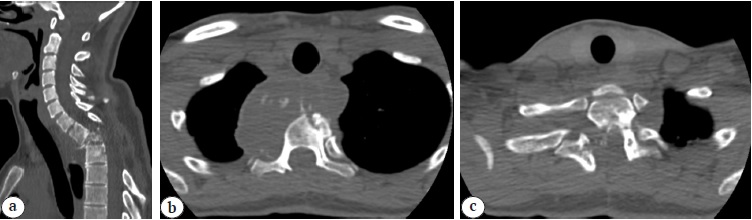

Radiological examination (multispiral computed tomography [MSCT] and MRI) revealed total Th1 body destruction, pre- and paravertebral, epidural cystic formations, and postlaminectomy cervicothoracic kyphosis of the spine of 56° according to Cobb. The nature of destructive changes and cystic formations was regarded as spinal echinococcosis recurrence (Fig. 1, 2).

Fig. 1. CT images at the time of hospital admission: a — sagittal view: Th1-2 destruction, angular cervico-thoracic kyphosis 56° Cobb; b, c — axial view: paravertebral cyst, mainly located in the right paravertebral side, postlaminectomy defect С7-Th4